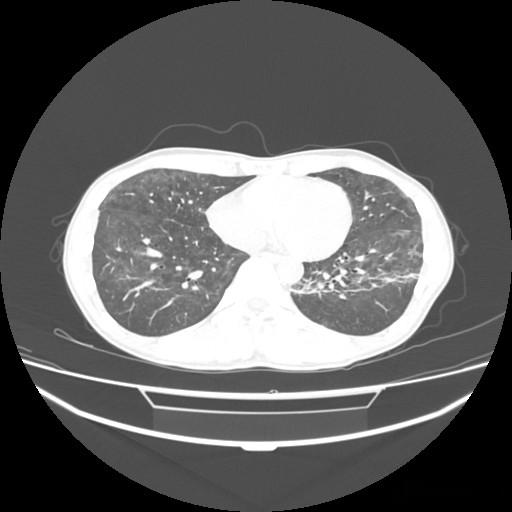

肺孢子菌肺炎(PCP)曾是艾滋病患者的致命杀手,如今已成为诊断艾滋病的重要指标之一。这种真菌感染在20世纪80年代初首次引起医学界的广泛关注,当时它几乎只出现在艾滋病患者身上。随着医学的进步,PCP的诊断和治疗有了显著改善,但它作为艾滋病“哨兵”的角色却愈发重要。

PCP之所以成为艾滋病的标志性疾病,与其独特的发病机制密切相关。肺孢子菌是一种常见的环境真菌,在健康人的免疫系统面前通常不会引起疾病。然而,当人体免疫系统受损,尤其是CD4+T细胞计数低于200个/μl时,这种真菌就会趁虚而入,引发严重的肺炎。在未经治疗的艾滋病患者中,PCP的发病率可高达70%以上。

在艾滋病的诊断和治疗中,PCP扮演着重要角色。根据美国CDC的定义,CD4+T细胞计数低于200个/μl或出现某些机会性感染(如PCP)即可诊断为艾滋病。因此,PCP不仅是艾滋病的并发症,也是诊断艾滋病的重要依据之一。对于疑似艾滋病的患者,如果出现不明原因的发热、咳嗽、呼吸困难等症状,医生往往会考虑进行PCP的相关检查。

PCP的出现不仅提示艾滋病的存在,还预示着患者免疫系统的严重受损。研究显示,PCP患者的CD4+T细胞计数通常低于50个/μl,这意味着他们的免疫系统已经处于极度脆弱的状态。因此,PCP的诊断往往伴随着紧急的抗病毒治疗和免疫重建治疗。